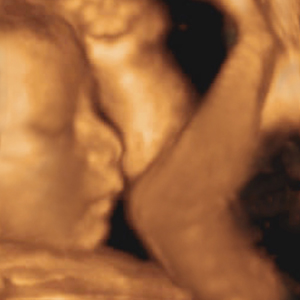

胎兒寫真“胎兒寫真”是用四維彩超技術照出來的,四維彩超確實能看到胎兒的鼻樑、眼睛和手腳的輪廓,但只是一個大概的影像,效果還不如黑白照片,更談不上“寫真”;況且全身照會透露胎兒的性別,即使能得到一張模糊的照片,也只能是胎兒的半身照。

自20世紀60年代以來,超音波檢查已成為產前孕婦例行檢查的一個重要環節。它利用超音波的物理特性和人體組織結構的聲學特點,將胎兒的影像顯示在監視屏上,進行動態觀察,可替早期懷孕婦女評估懷孕周數、診斷早期懷孕異常、診斷多胞胎、檢測出子宮及卵巢異常、評估胎兒發育狀況等。

面對質疑,很多醫院方面表示,孕婦做四維彩超進行胎兒篩查,不會對孕婦造成任何影響,而且可以篩查出胎兒會不會有肢體畸形、唇齶裂等多種疾病,對於優生優育具有一定的指導作用。同時,在拍攝“寫真”時,醫生也會選擇角度,迴避胎兒下半身,在列印照片和刻錄光碟時,也會進行技術處理,不會透露胎兒性別。

胎兒寫真世界衛生組織早在1982年就已建議:只有在醫學上具有明確理由時,才可對人體使用超聲診斷;不應以商業和實驗為目的輻照人體,特別是輻照孕婦。超音波是一種能量,現在已經用於殺滅腫瘤細胞和人體碎石,超過一定劑量(強度和時間)肯定會對人體造成傷害。

胎兒寫真醫學界已證實,有專門證書的醫學專業人士按嚴格科學規程進行的超音波檢查是安全的診斷手段,對胎兒無害。

不過,對於給胎兒拍照這種商業和娛樂做法,醫學界普遍表示反對。美國“醫療診斷超音波掃描協會”、“孕婦-胎兒醫療協會”和美國婦產科學院的醫生強調,超音波是一種醫學程式,並非照相的選擇。如果未經培訓、無人監管的技師自稱發現胎兒的缺陷,或者孕婦過度相信“攝影師”而懷疑醫生,都可能產生不良後果。